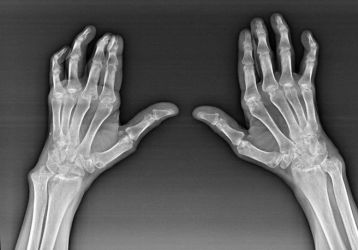

Полиартрит пальцев рук: симптомы, диагностика, лечение, полное описание недуга

Полиартрит рук: причины и типы заболевания, стадии и симптомы, диагностика. Народное и медикаментозное лечение полиартрита кистей рук, образ жизни и диета.